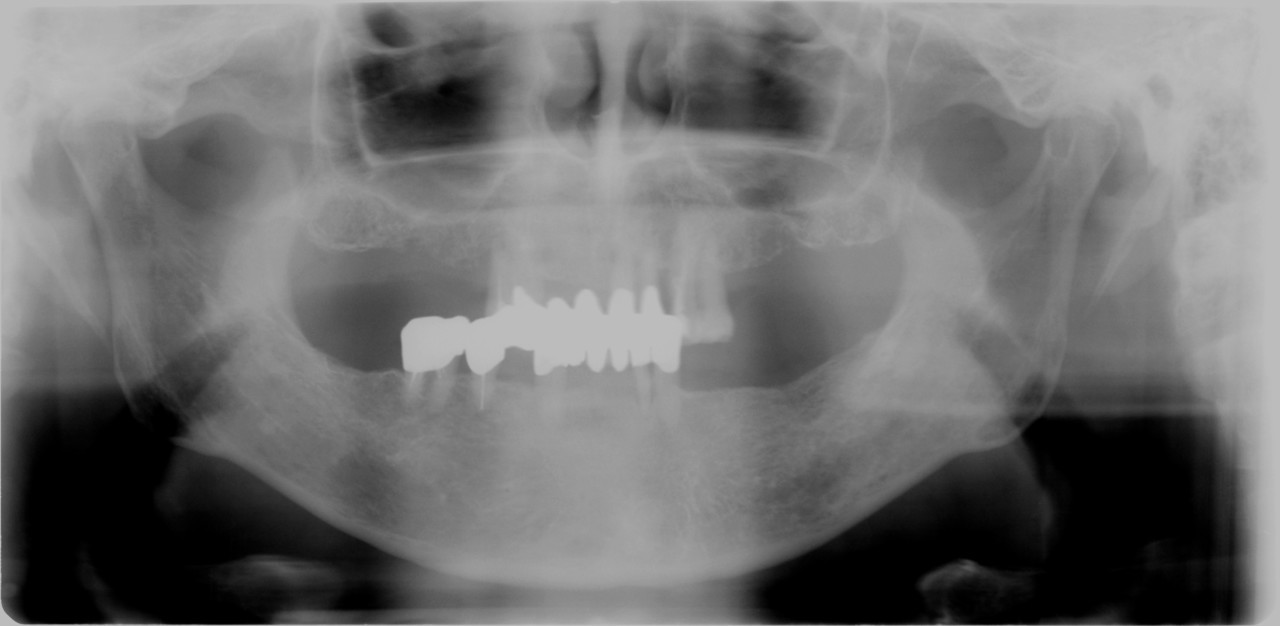

【審美歯科・奥歯症例】

●白い歯(セラミックス)

ハイブリッドクラウン 3本

上記費用目安

初診検査 3500

グラスファイバーコア 20000×2本 15000×1本

仮歯 2000×3本

歯型 5500

ハイブリッドセラミック 39800×3本

調整装着費用 5500

■ポイント■

比較的安価で白い歯が可能、やや耐久性に問題があり

噛み合わせ強い方や歯ぎしりのある方は適応から外れる

奥歯では十分なキレイさ(審美性)

費用が比較的安い

セラミックに比べて 見た目や耐久性は劣る